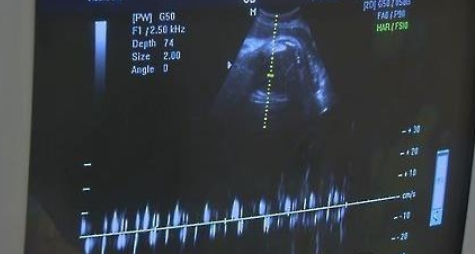

A씨의 후배에게 둘째가 생긴 이유는 정관이 여러 다발이었기 때문이다.

보통은 정관이 한 줄기지만, A씨의 후배는 독특한 구조를 가지고 있었던 탓이다.